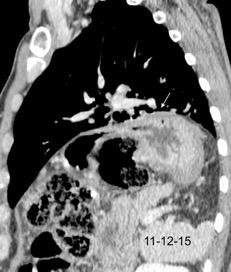

T. mixto de células germinales del testículo izquierdo

Nódulos pulmonares múltiples. (flechas verdes). Masas paratraqueales. (flechas amarillas). Dudoso ensanchamiento retrocrural (flechas negras). sigue….

Ttawfik A et al. Trans-diaphragmatic Pathologies: Anatomical Background and Spread of Disease on cross-sectional Imaging. Current Problems in Diagnostic Radiology. 2021.

T. mixto de células germinales del testículo

izquierdo Metástasis pulmonares. (flechas verdes). Ganglios paratraqueales. (flechas amarillas). Ganglios retroperitoneales (flechas negras)

Tawfik A et al. Trans-diaphragmatic Pathologies: Anatomical Background and Spread of Disease on cross-sectional Imaging. Current Problems in Diagnostic Radiology. 2021.